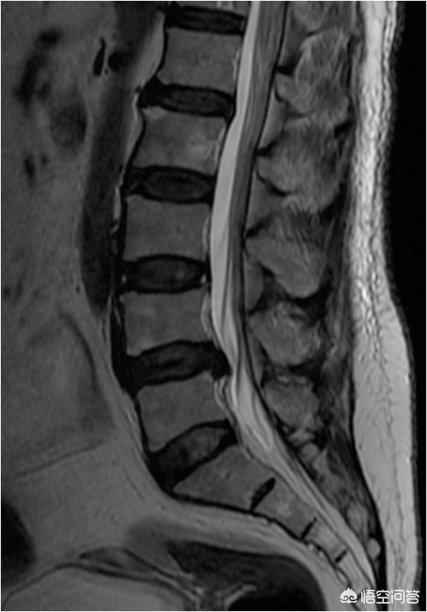

En clinique depuis de nombreuses années, j'ai vu de nombreux patients souffrant de protrusion lombaire, dont beaucoup ne présentent aucun symptôme, ce qui, aux yeux des personnes extérieures, est incroyable. Après tout, l'examen de la colonne lombaire a montré une protrusion, mais aucun symptôme ; et la taille de la protrusion et le degré des symptômes (douleur) ne sont pas directement liés, de nombreux patients souffrent de douleurs insupportables au début, mais après une période de traitement conservateur, le symptôme est progressivement soulagé ! De nombreux patients ont des douleurs intenses au début, et après une période de traitement conservateur, les symptômes s'atténuent progressivement, voire disparaissent, mais s'ils passent une IRM, ils peuvent constater que la hernie discale lombaire n'a pas diminué.

Ce n'est pas magique ; en fait, les patients souffrant de protrusions lombaires bénéficient d'un soulagement des symptômes grâce à la réduction de l'irritation et de la réponse inflammatoire associée à la hernie qui appuie sur la racine nerveuse.